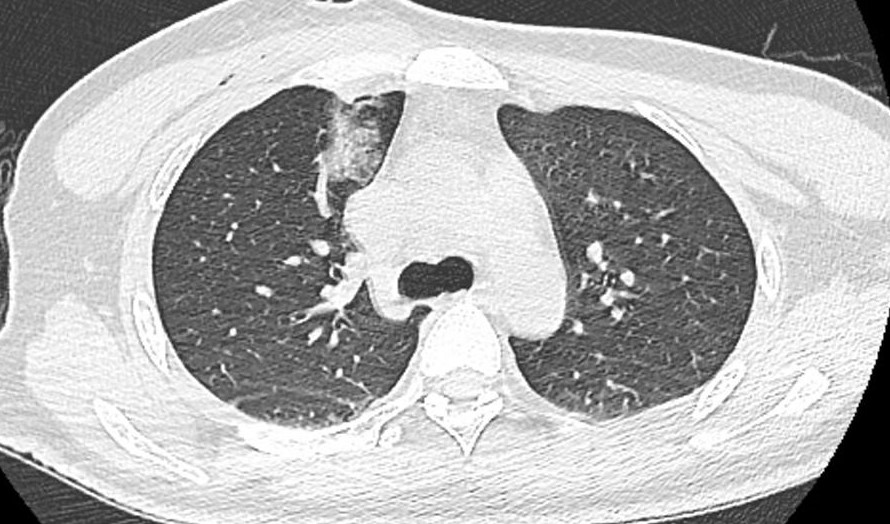

(箭头所指处:结节消融完全,周围被包绕,未见明显出血及气胸征象)